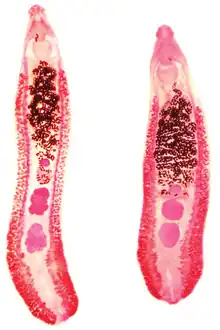

| Two specimens of Echinostoma revolutum | |

Echinostoma is a genus of trematodes (flukes), which can infect both humans and other animals. These intestinal flukes have a three-host life cycle with snails or other aquatic organisms as intermediate hosts,[2] and a variety of animals, including humans, as their definitive hosts.

Echinostoma are internal digenean trematode parasites which infect the intestines and bile duct[4] of their hosts.

The length and width of adult Echinostoma varies between species, but they tend to be approximately 2-10mm × 1-2mm in size.[5]

Adult Echinostoma have two suckers: an anterior oral sucker and a ventral sucker.[4] They also have a characteristic head collar with spines surrounding their oral sucker.[6] The number of collar spines varies between Echinostoma species, but there are usually between 27 and 51.[4] These spines can be arranged in one or two circles around the sucker, and their arrangement may be a characteristic feature of an Echinostoma species.[4]

Echinostoma have a digestive system consisting of a pharynx, oesophagus and an excretory pore.[4]

Echinostoma are hermaphrodites,[6] and have both male and female reproductive organs. The testes are found in the posterior part of the fluke's body, in the area furthest from the mouth.[4] The ovary is also found in this location, close to the testes.[4]